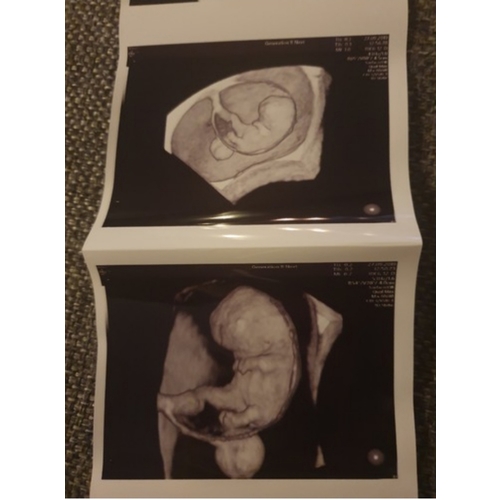

Ik heb er twee gehad in dezelfde week. Eentje was een 3d echo en eentje een 2d bij de gynaecoloog. Ik vond dit buiten beetje oncomfortabel na een tijdje geen probleem. Vooral met de 3d echo lag ik er echt een halfuur. De echo's waren gemaakt met 8 weken.